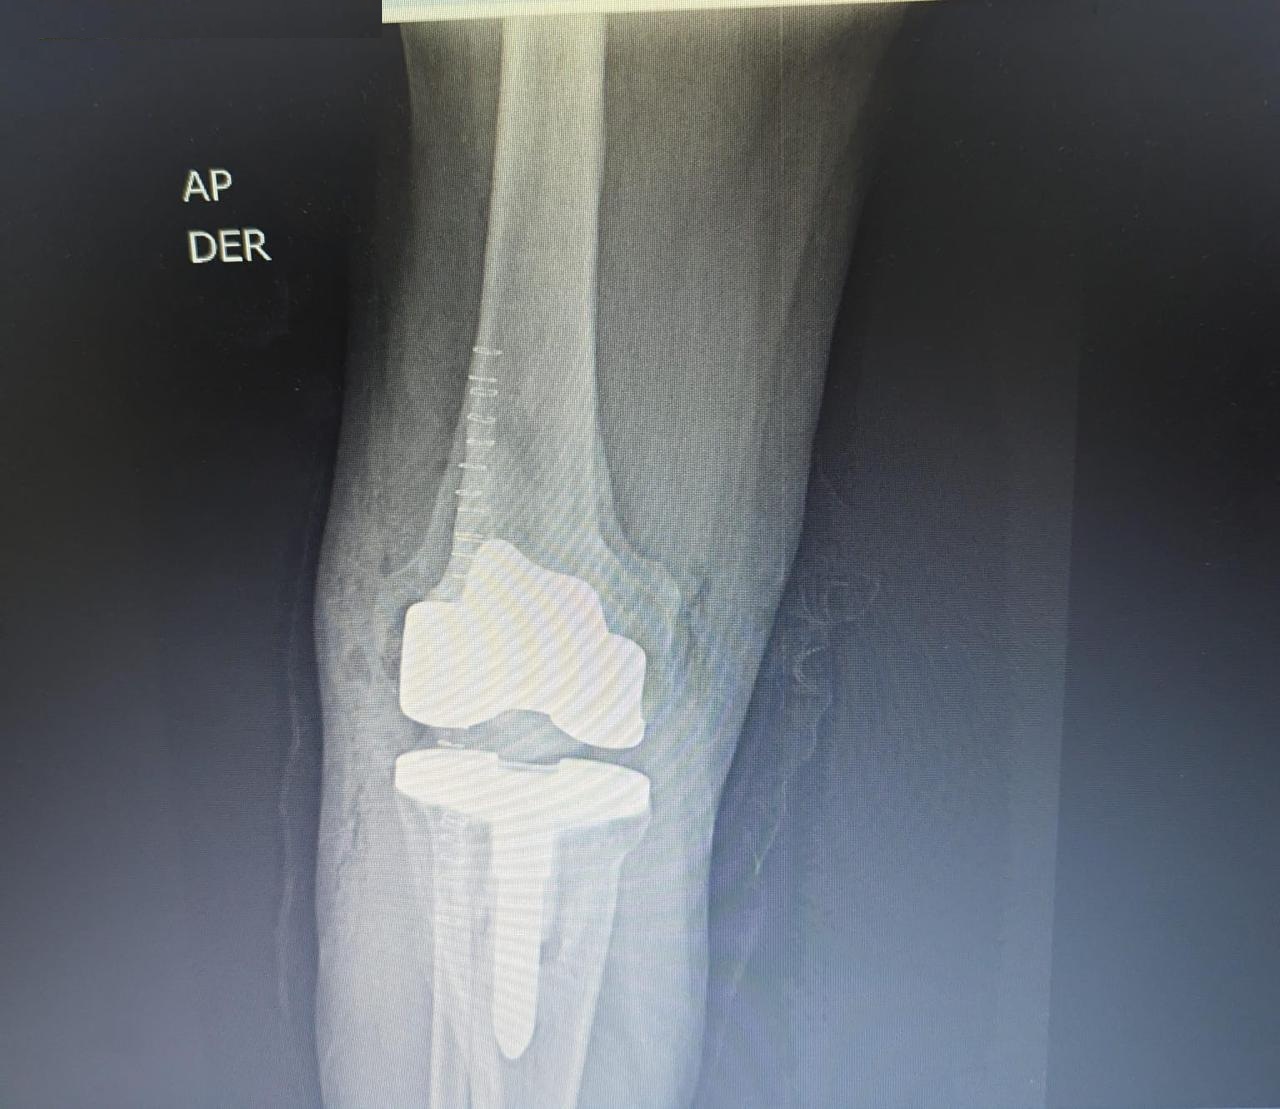

Después Radiografía postoperatoria de reemplazo articular de rodilla tras fractura de tibia

Traumatología

Reemplazo articular

Fractura de Tibia

• Perfil del Paciente: Masculino, 50 años.

• Historia Clínica: Antecedentes de 25 años de evolución con dolor crónico y pérdida de movilidad.

• Diagnóstico: Osteoartrosis secundaria a fractura de rodilla antigua.

• Resultado (Caso 2024): Intervención exitosa con recuperación completa. Actualmente el paciente presenta una evolución óptima y retorno a su vida cotidiana.